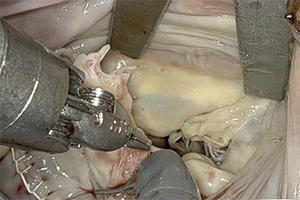

Vol 14, No 3 (May 31, 2025): Robotic Aortic Valve Replacement